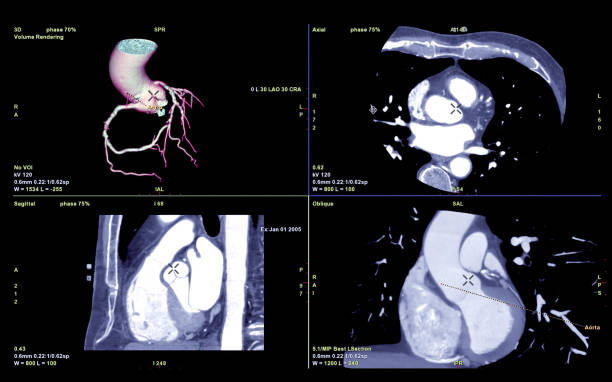

관상동맥 석회화를 검사하기 위해 CT 검사를 사용합니다. 이 검사로 석회화된 혈관 내 벽의 정도와 범위를 확인할 수 있으며, 석회화 양을 수치로 계산할 수 있습니다. 일반적으로 석회화 수치는 0점부터 시작하며, 수치가 높을수록 중증의 석회화를 의미합니다.